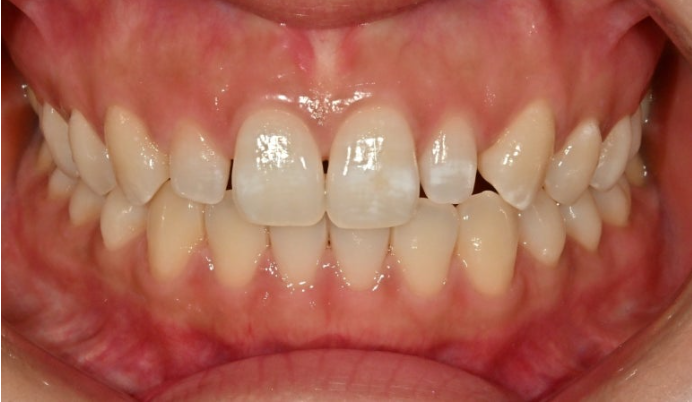

어쨌든 환자분은 치열이나 교합은 완벽하여 별도의 교정치료는 필요가 없는 상태입니다.

다만 앞니 전반에 퍼져있는 흰색 얼룩, 즉 반점치가 있는 상태입니다.